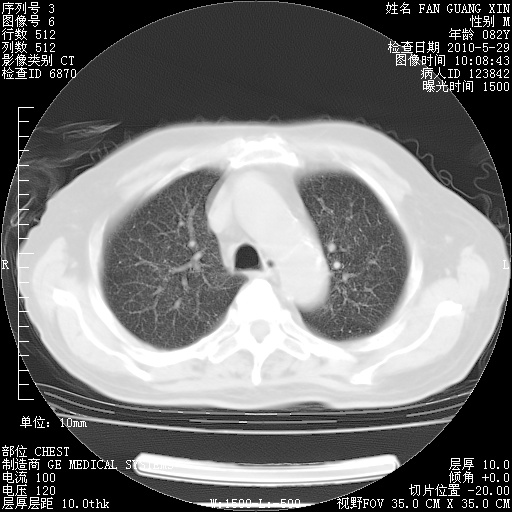

再治疗10天后的肺部CT

阅读此次胸部CT,肺间质渗出性改变较入院时有吸收。目前从体温、白细胞、中性分叶明显增高,肯定存在细菌感染(发生医院感染哦,若无消化道及泌尿系统等感染的依据,肺部感染可能大)。若你院头孢哌酮舒巴坦钠耐药率较高,同意你的方案,若48小时体温仍高,可考虑使用碳青霉稀类抗菌药物,同时可予超声雾化、注意滴数时加大液体量。白蛋白33.30g/L较低哦,需加强营养等支持治疗。

从白细胞总数和中性比例看好像合并感染。肺部纹理好像比上次多,支气管炎?其他感染?